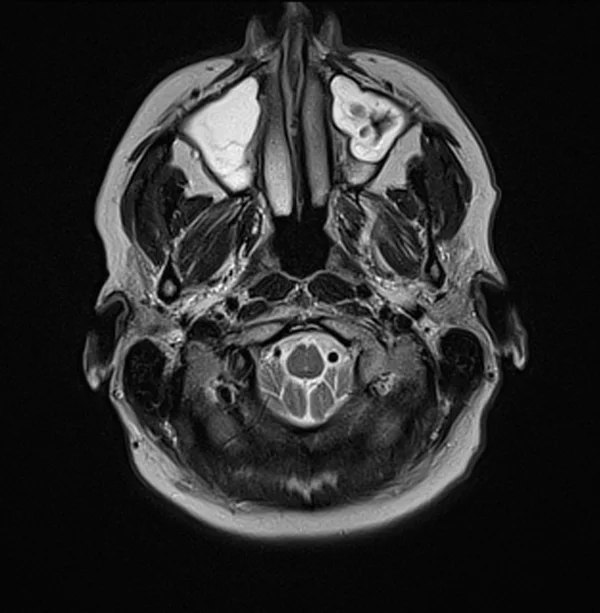

Brain MRI T2 axial images